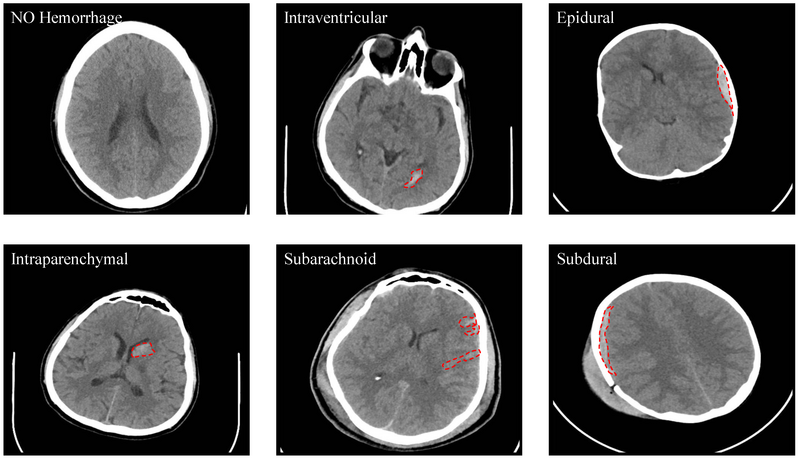

Abbildung: Hssayeni, Murtadha D., Muayad S. Croock, Aymen D. Salman, Hassan Falah Al-khafaji, Zakaria A. Yahya, and Behnaz Ghoraani. 2020. "Intracranial Hemorrhage Segmentation Using a Deep Convolutional Model" Data 5, no. 1: 14. https://doi.org/10.3390/data5010014

Abbildungsunterschrift: CT-Bilder des Kopfes: KI-Systeme können bei der schnellen Diagnose von Hirnblutungen anhand solcher Bilder unterstützen.